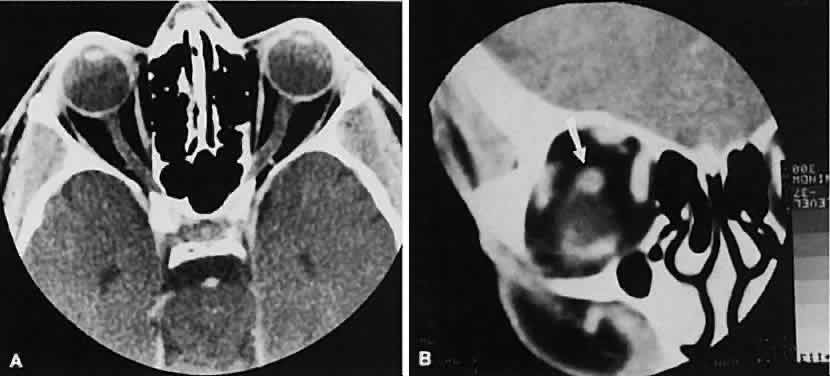

The edema and inflammatory infiltrate that accompany infections are indistinguishable from that associated with orbital inflammations. The presence of sinus disease, however, is a more constant feature with infections, because the sinus represents the infectious nidus in most cases (Fig. 9). In addition to the frequent appearance of sinus disease, the adjacent EOM is invariably enlarged. Less often, orbital infections may be transmitted through the blood, related to a retained foreign body, or spread from the lids. Chandler and colleagues47 classified orbital infections into five groups. Group 1 (preseptal cellulitis) represents inflammatory edema and reflects congestion of venous outflow. Group 2 has actual orbital infiltration/edema with mass effects and functional deficits. Group 3 includes patients with subperiosteal abscesses. Most of these dome-shaped subperiosteal abscesses are located along the medial wall. Group 4 includes patients with orbital abscesses who may display a ring-enhancing lesion with mass effect. Group 5 represents intracranial extension of the inflammation into the cavernous sinus or sinuses, which appear engorged and opacified.

Fig. 9. Orbital cellulitis. A. Axial view shows a subperiosteal soft-tissue mass displacing the medial rectus muscle. The ethmoidal sinus is opacified secondary to inflammatory disease, which invariably precedes the orbital inflammation. B. Coronal view further shows the subperiosteal and ethmoidal sinus inflammation. Inflammation changes also are seen in each maxillary sinus.